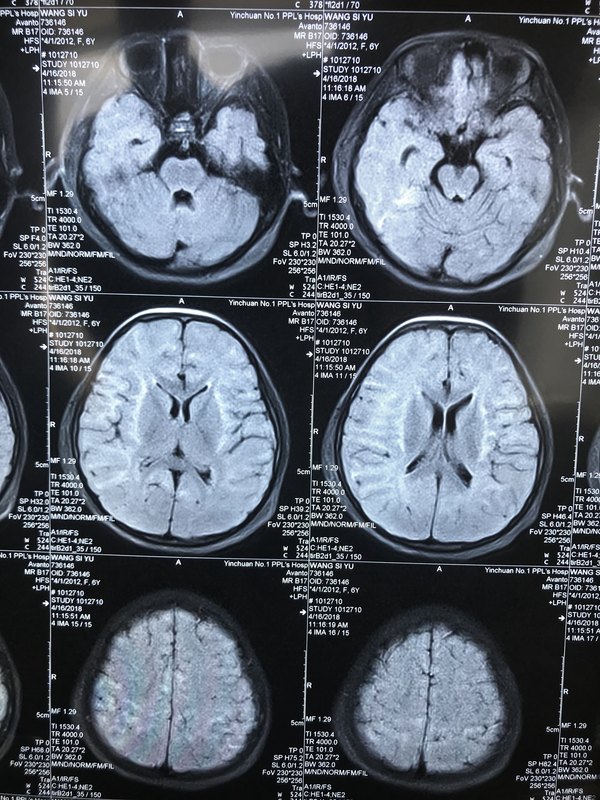

診治經(jīng)驗(yàn)分享患兒、女、6歲10個(gè)月,主因“發(fā)熱3天,抽搐1次”入院。入院時(shí)神志清,咽部充血,扁桃體腫大,心、肺、腹部及神經(jīng)系統(tǒng)檢查未見異常。入院當(dāng)天再抽搐1次,腦脊液壓力增高,常規(guī)、生化、涂片及培養(yǎng)均正常,頭顱CT未見異常,肺部CT提示雙肺紋理增強(qiáng),血白細(xì)胞正常,中性粒細(xì)胞增高,血CRP略增高,肝、腎、功能及血電解質(zhì)正常,單純皰疹病毒IgG陽性,入院后給予阿昔洛韋抗病毒、甘露醇、呋塞米降顱壓及補(bǔ)液治療。入院第2天出現(xiàn)頻繁抽搐,意識(shí)障礙逐漸加重,入院第4天進(jìn)入深昏迷狀態(tài),給予無創(chuàng)呼吸機(jī)輔助通氣,腦電圖提示有較多量癇樣放電,給予左乙拉西坦抗癲癇治療抽搐無改善,又聯(lián)合妥泰治療,抽搐減少,但持續(xù)高熱,隨后出現(xiàn)重癥肺部感染、上消化道出血,酸堿平衡及電解質(zhì)紊亂,又給予美羅培南抗炎治療,止血敏止血,靜脈丙種球蛋白,全靜脈營養(yǎng),亞低溫治療,維持內(nèi)環(huán)境穩(wěn)定,體溫正常后做顱腦核磁提示符合單純皰疹病毒性腦炎改變,經(jīng)過積極的搶救,患兒于昏迷12天后蘇醒,抽搐完全緩解,剛蘇醒時(shí)失語、吞咽功能明顯減弱,不能進(jìn)食,雙上肢肌力3級(jí),雙下肢肌力1級(jí),雙下肢肌張力增高,給予康復(fù)訓(xùn)練,現(xiàn)治療4周,患兒可以下地走路,吞咽功能恢復(fù)正常,語言交流比較流暢,認(rèn)知水平基本接近發(fā)病之前,患兒已康復(fù)出院。